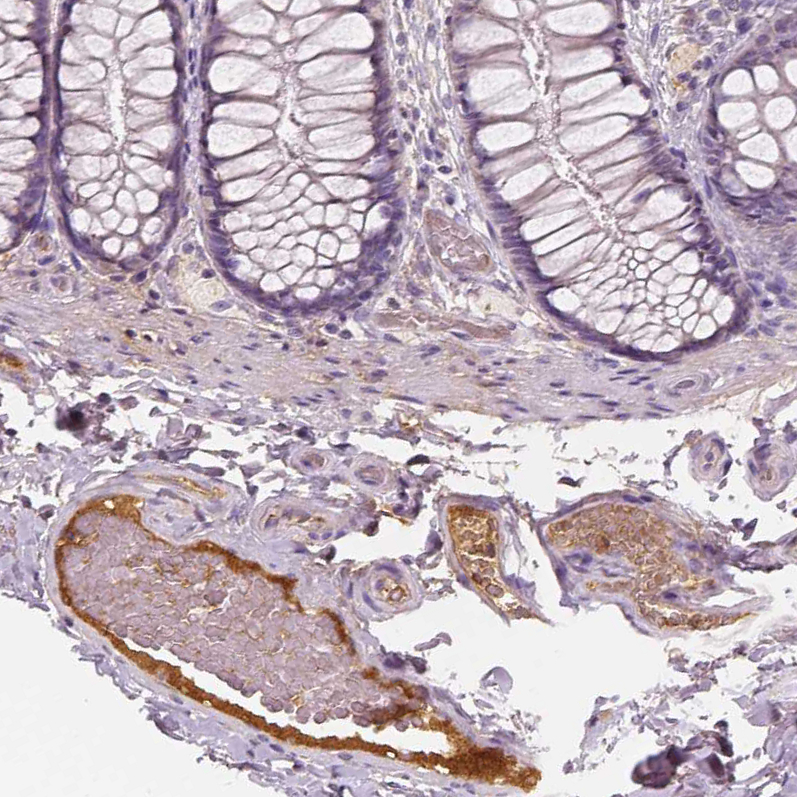

Immunohistochemistry analysis in human small intestine and pancreas tissues using AMAb90767 antibody. Corresponding APOA4 RNA-seq data are presented for the same tissues.